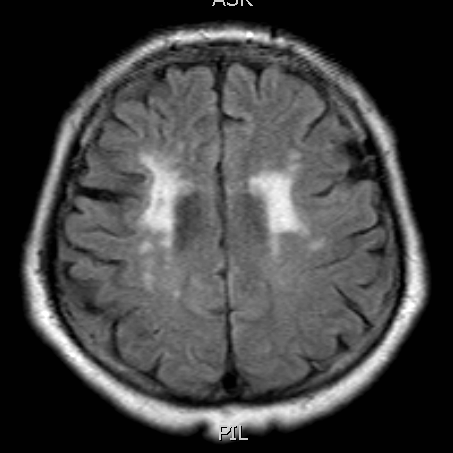

Flair

右侧相对低灌注